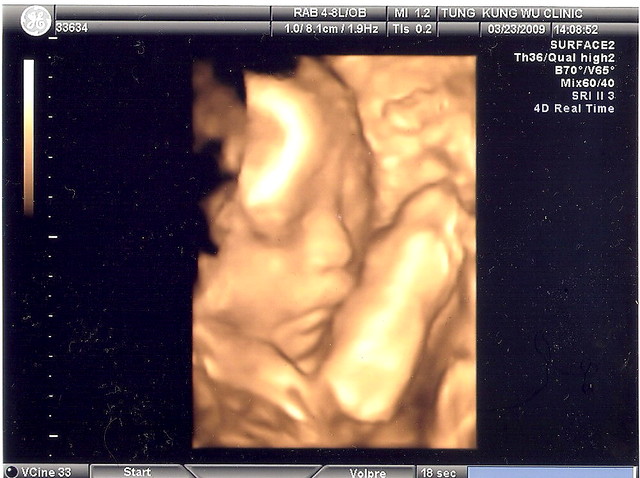

4D照片是小茄子在我肚子二十四的模,他睡得很熟,仔瞧瞧,是不是和羊ㄇㄟ ㄇㄟ得很像呀?!